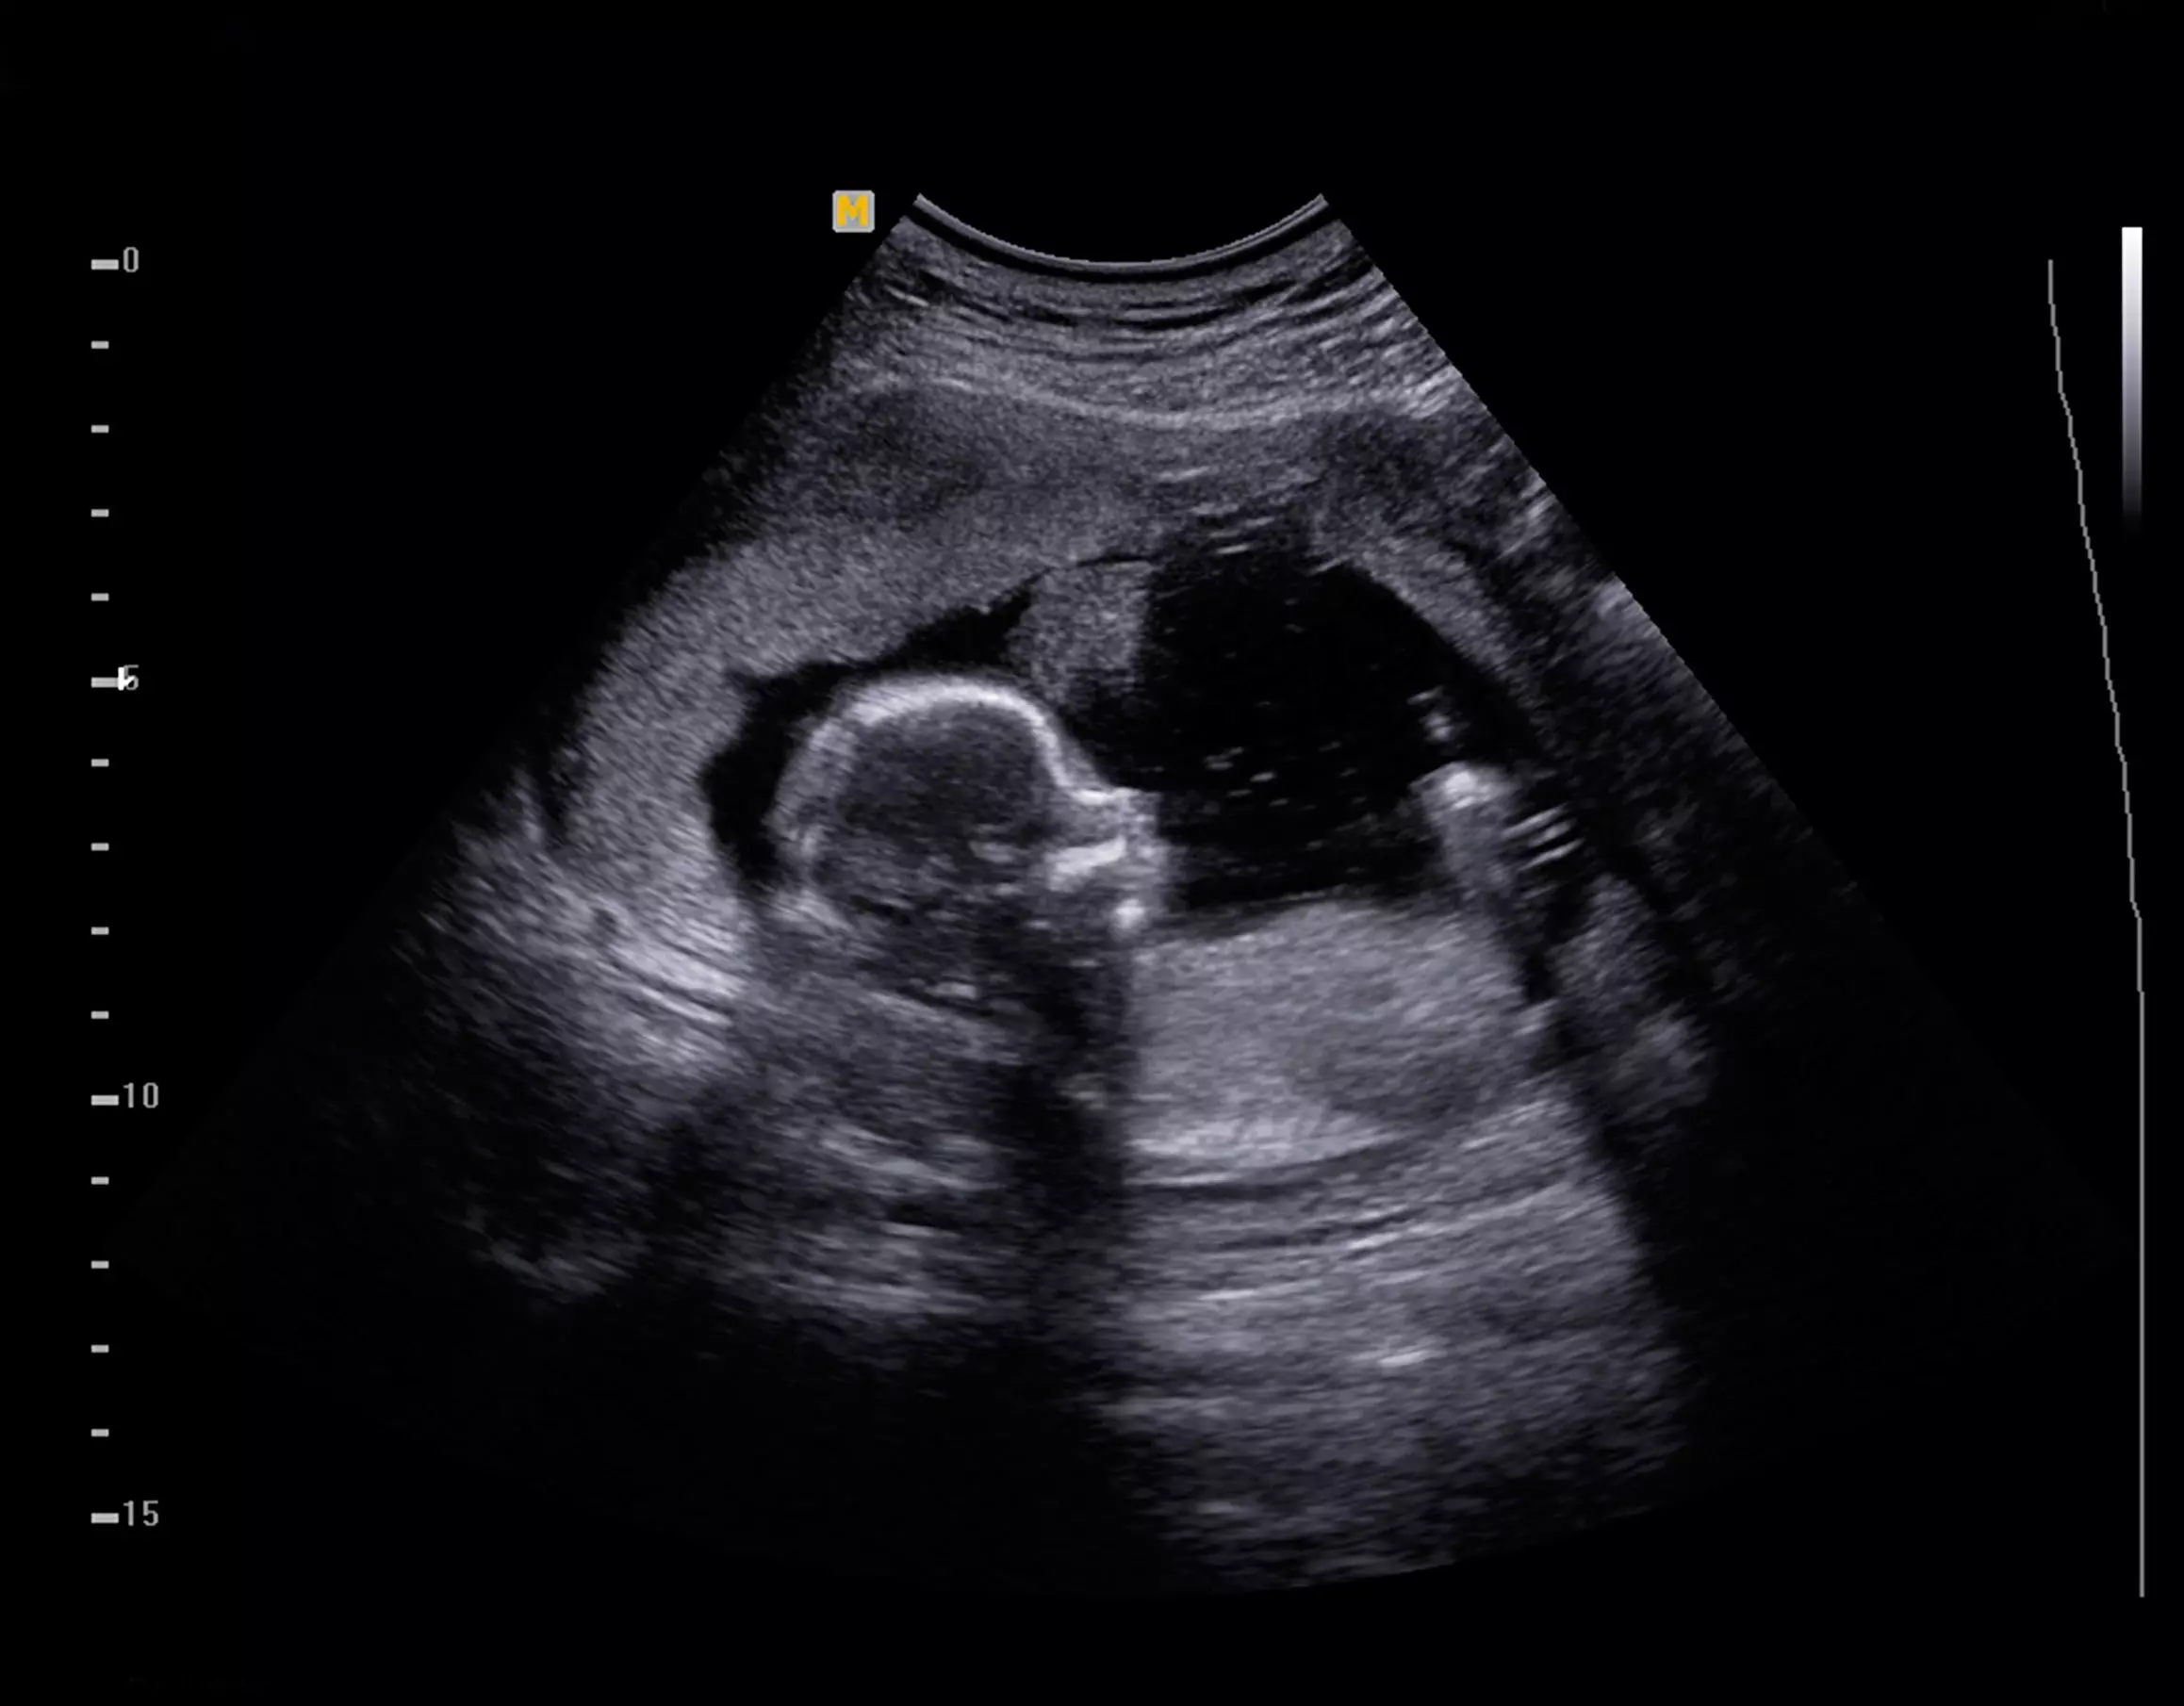

“As Healthcare professionals we are totally aware of the science of human development. The humanity of a 22-week fetus is apparent to each of us. There can be no doubt that the 22-week fetus is fully alive and fully human,” the letter reads.

In their letter, released last week, the 134 health care professionals and scientists outlined facts of fetal development that illustrate the humanity of an unborn baby at 22 weeks.

Babies at this age may react to their mother’s touch, experience pain, and demonstrate a preference for their mother’s voice, as well as for musical pieces to which they have been exposed. Children at this age may even exhibit social interaction with a twin in utero.

Advances in neonatal medicine mean that babies born at 22 weeks are often able to survive, the signers of the letter said. They noted that some medical centers in the U.S. have a 70% survival rate for premature babies born at this age.

A fetus can also undergo surgery, and is treated as a separate and distinct patient from the mother, the doctors and scientists noted, adding, “Therefore, they should be treated as individuals by Colorado law.”